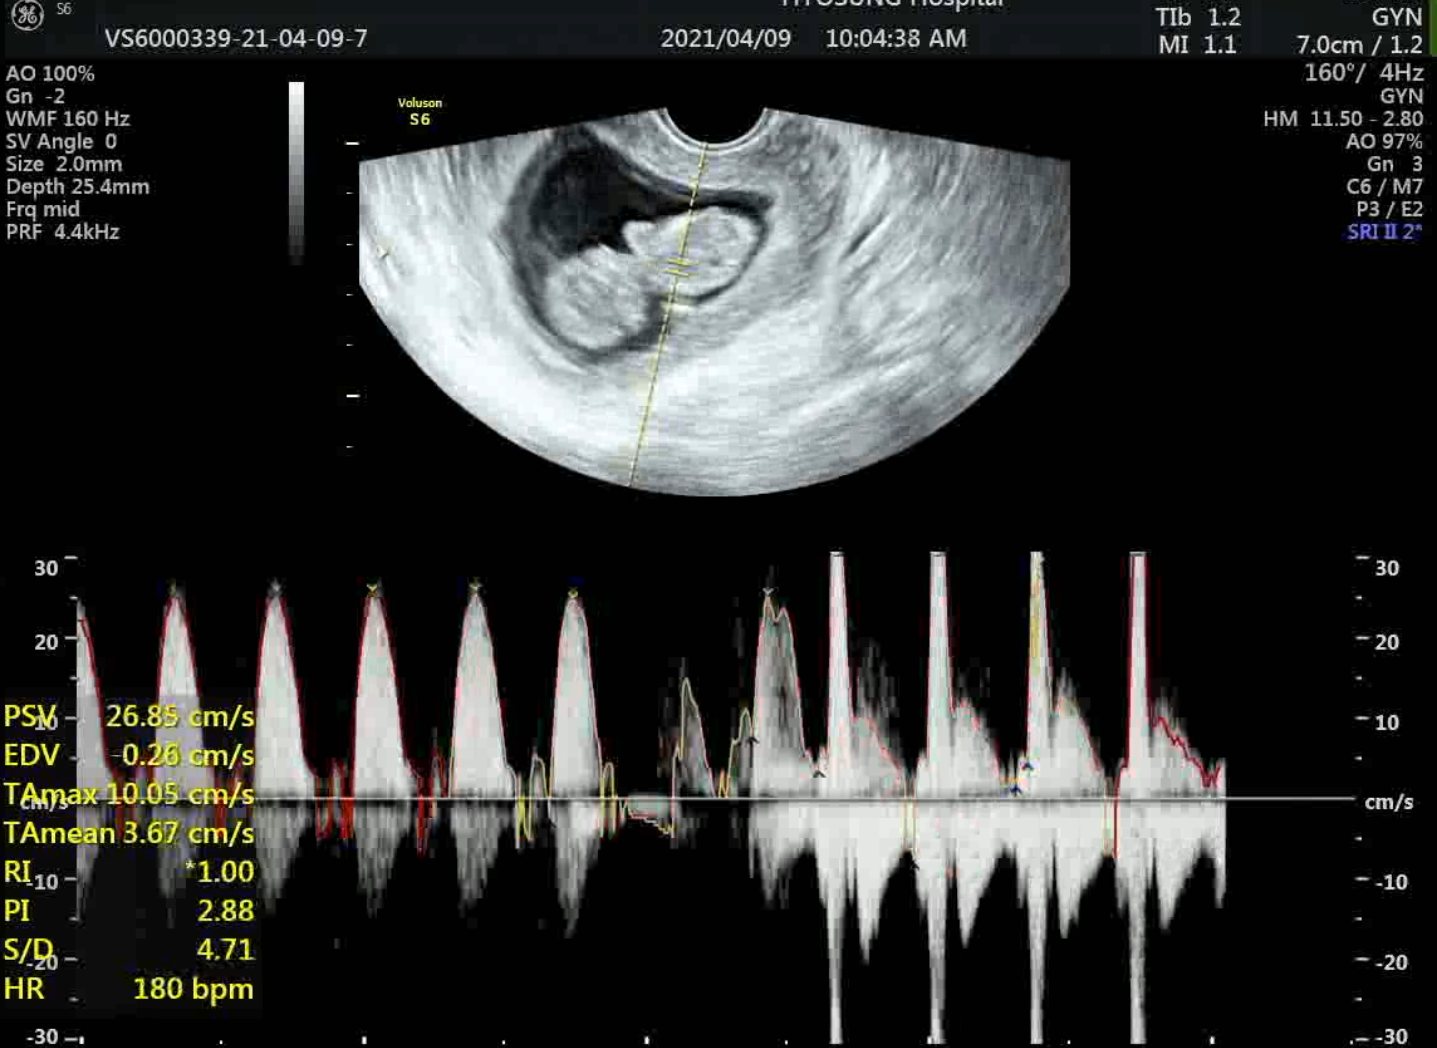

와이프 나이가 있다보니깐 사실 이제 애 안 생길 줄 알았는데.

하늘이 주신 건가?

좀 걱정은 되는구만 . 워낙 고령 임신이라서 애기랑 산모랑 건강해야할텐뎅